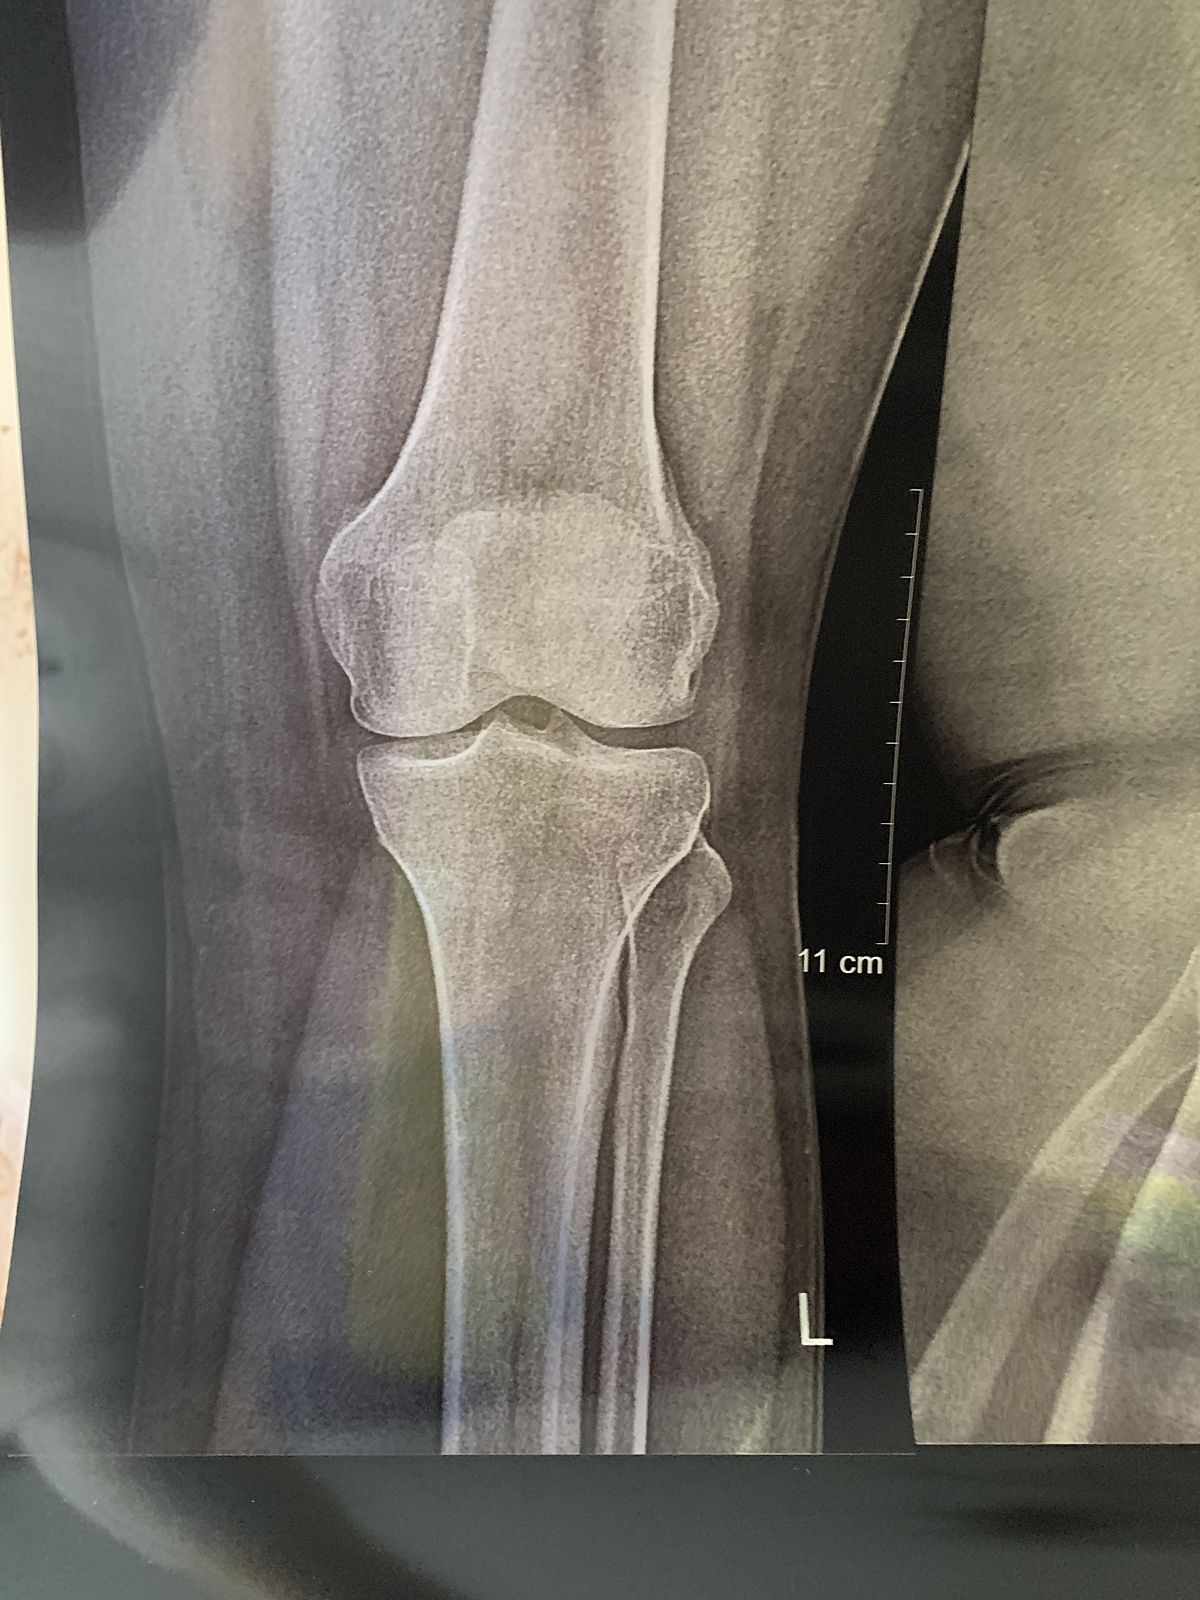

Колено. Результат рентгена

Далеко не начало если ставят остеоартроз, суставная щель сужена, но это только рентгенологически, заключение должен дать травматолог, а сам снимок где?

Вот

Нет. В одном месте больно если нажать. По утрам периодически тяжесть в ногах, но минут 10-15 рассаживаюсь и все ок. Ходу нормально никаких обезболивающих не принимаю

В любом случае за 2 недели хуже не станет, травматолога посетить нужно обязательно